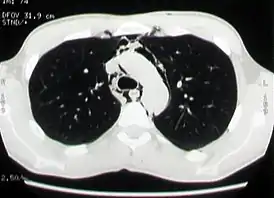

![]() КТ-изображение: эмфизема средостения у больного со спонтанным пневмомедиастинумом | |

Компьютерная томография органов грудной клетки

Компьютерная томография является наиболее эффективным методом диагностики эмфиземы средостения, так как с его помощью легко выявляется наличие газа в средостении, на поперечных сечениях хорошо определяется его локализация и распространённость эмфиземы. Преимуществом перед рентгенографией является возможность диагностики пневмомедиастинума даже в тех случаях, когда имеется выраженная эмфизема мягких тканей грудной стенки, сводящая информативность рентгенографии в этой ситуации к минимуму. Кроме того, компьютерная томография позволяет провести дифференциальную диагностику спонтанного пневмомедиастинума и других заболеваний с похожей клинической картиной, а также важна для установления причины заболевания[2][21].